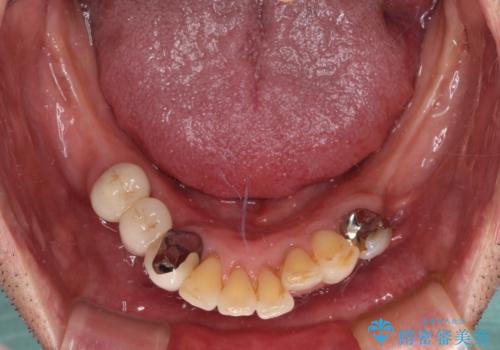

- 以前入れ歯を製作したものの、装着感が悪く使用できなかったとのことで来院された患者様です。

インプラントによる治療プランも提案しましたが、インプラントは避けたいとのご希望であったため、入れ歯による補綴治療を行うこととしました。

自費治療の義歯は装着感がとても良いですが、急に入れ歯を装着すると、異物感が強く継続使用できなくなるため、仮歯の期間中に保険治療での義歯を装着してもらい、口腔内を義歯に慣れさせるようにしました。